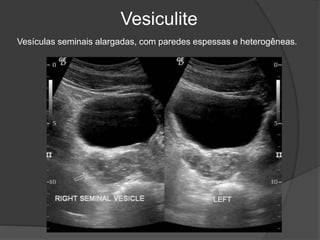

Vesiculite

Vesículas seminais alargadas, com paredes espessas e heterogêneas.